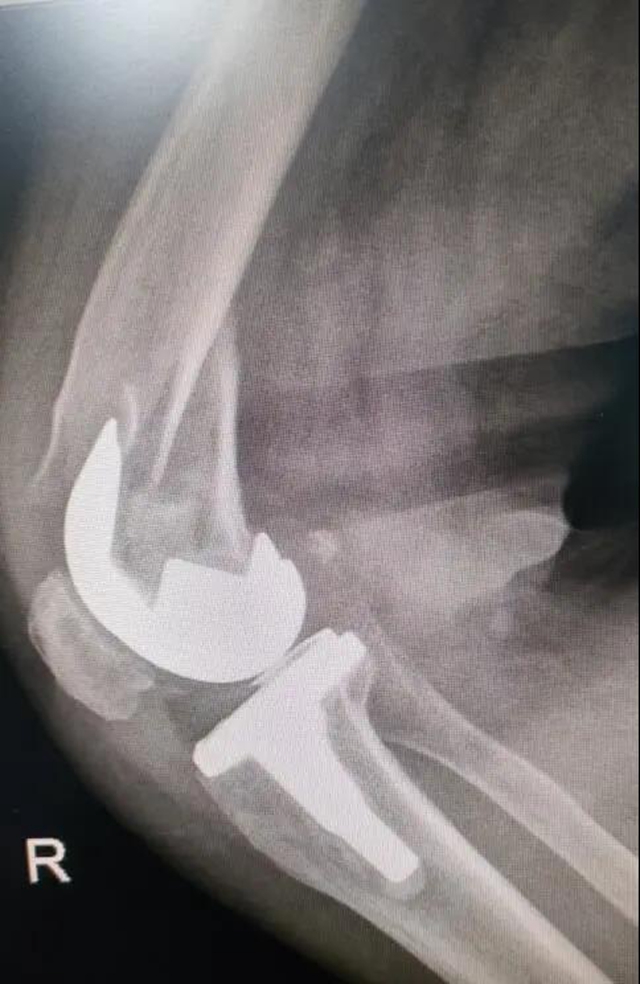

术前

骨折部位在假体周围,患者还患有严重的内风湿、骨质疏松、高血压……能否耐受这台复杂而高难度的关节翻修与骨折手术?这对医院骨伤三科医护团队来说,是一个不小的挑战。

“关节假体需要进行‘翻修’固定,要保证骨折部位修复后假体的稳定性,还要考虑患者年龄大,曾接受过多次手术,患有多种基础疾病,手术技术难度高,对医生和患者都是一次挑战。”作为手术团队成员和吴阿姨主管医生的王旌晶觉得一定要对得起患者及家属这份沉甸甸的信任。